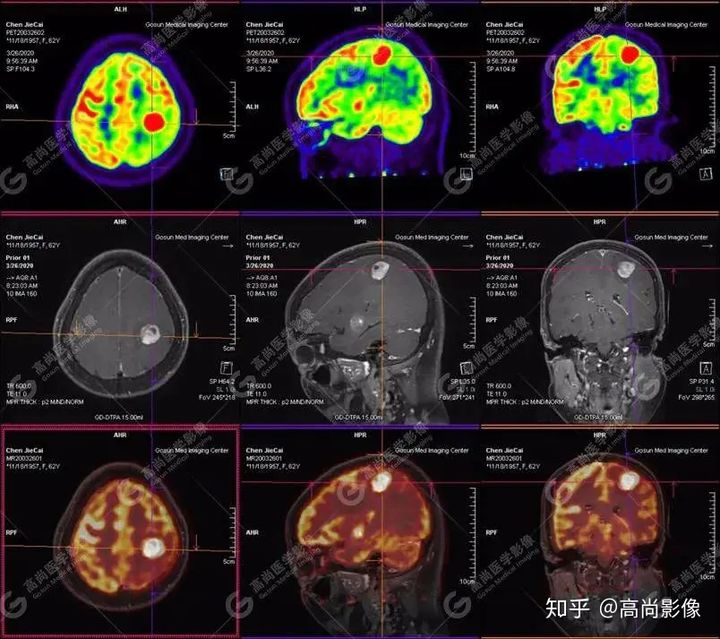

【PET-MR融合診斷】

左側(cè)顳葉、頂葉、左側(cè)基底節(jié)區(qū)及胼胝體部多發(fā)結(jié)節(jié)狀高代謝病灶,部分合并囊變、出血,MR平掃+增強(qiáng)示不均勻輕、中度強(qiáng)化,綜合考慮為顱內(nèi)原發(fā)惡性腫瘤,以淋巴瘤可能性大

淋巴瘤病變多位于中線兩旁的深部腦實(shí)質(zhì)、側(cè)腦室周?chē)澳X表面,甚少累及腦膜和顱骨,幕上多于幕下,呈分葉狀或握拳狀,水腫及占位效應(yīng)較輕,部分病灶內(nèi)可見(jiàn)囊變、出血及其邊緣的硬環(huán)征、尖角征、臍凹征,增強(qiáng)掃描呈現(xiàn)的“臍凹征或者“握拳征”是淋巴瘤較為特征性的一個(gè)表現(xiàn)。

18F-FDG PET PET顯像中呈明顯高代謝病灶。

顱內(nèi)惡性淋巴瘤對(duì)18F-FDG的攝取率很高,一般SUV在5~10以上,18F-FDGPET顯像中攝取明顯高于正常腦皮層,因此具有特征性。

PET/CT-MR檢查是原發(fā)顱內(nèi)惡性淋巴瘤的重要檢查方法,能有效提高診斷正確率;在早期發(fā)現(xiàn)、準(zhǔn)確分期、放化療后檢測(cè)具有極重要的作用。